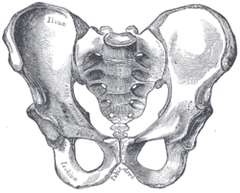

産後の骨盤矯正はとても重要です。 なぜ重要なのか、知っている方は少ないと思います。 お子さんを産んでから腰痛、肩こり、股関節痛や産後太りになってしまい、お悩みになる女性がとても多いのです。 そうならないためにも、産後の骨盤矯正が大切なことを説明したいと思います。 女性の骨盤(下左図)は男性(下右図)に比べ幅が広い形で骨盤が大きく、開いています。